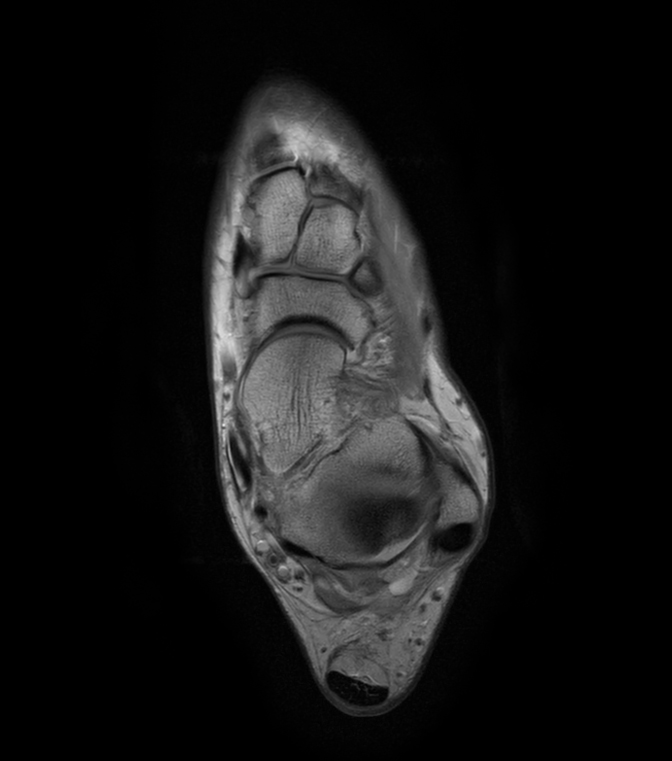

Imaging with the dS 16ch FootAnkle coil

General Hospital Sint Blasius, Dendermonde, Belgium

Patient who was referred for imaging of the achilles tendon